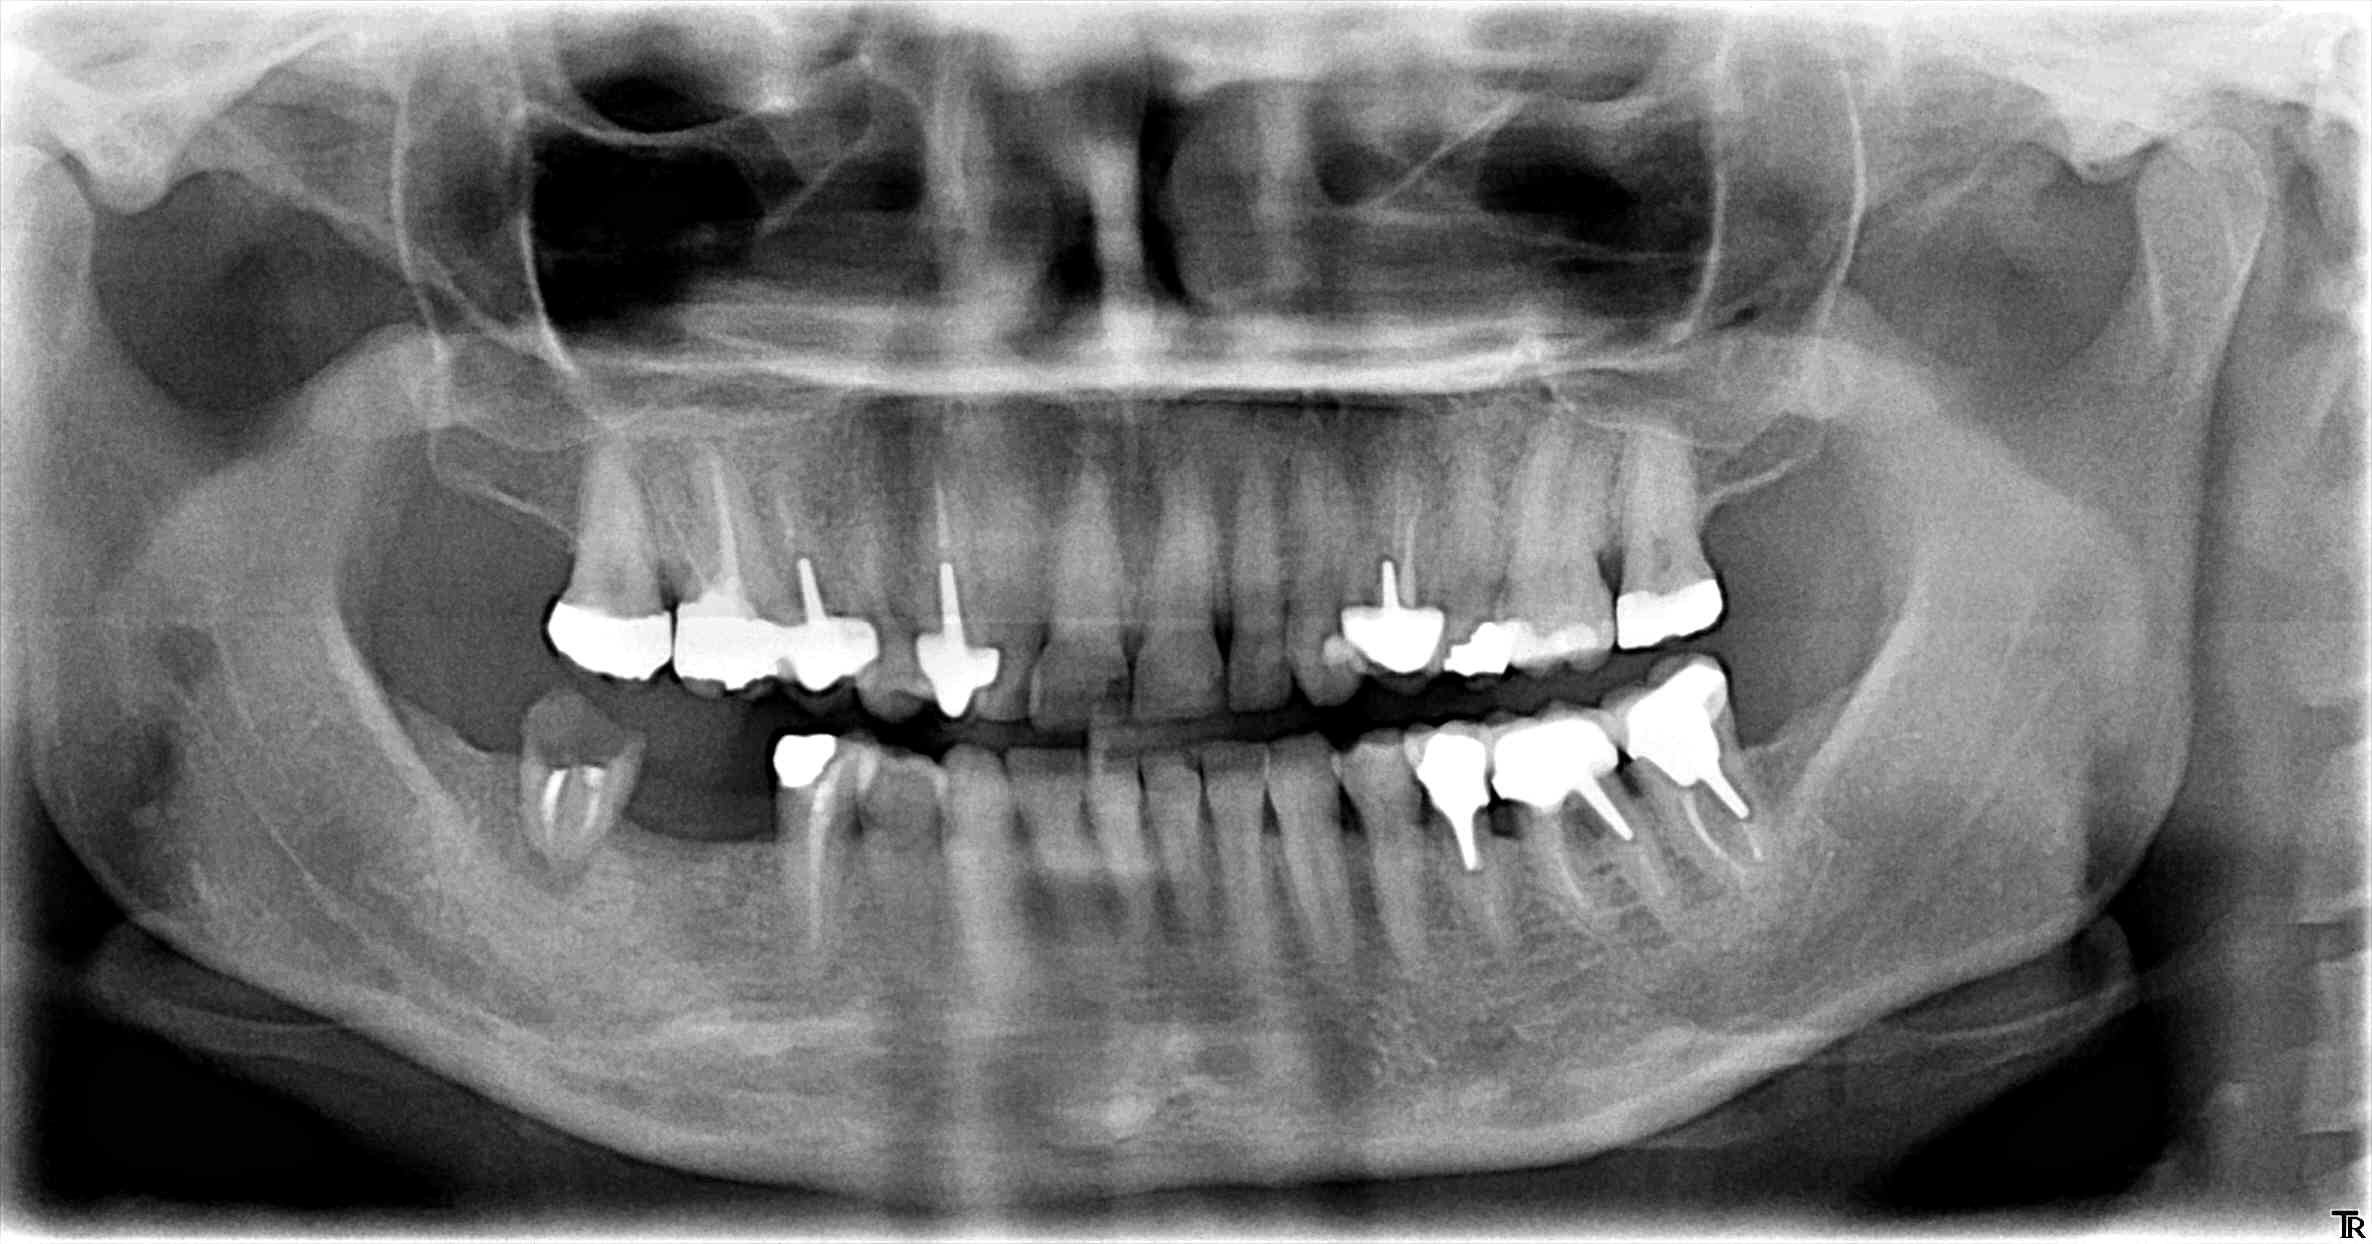

Ce viaduc, j'ai du le faire en 2008. depuis j'ai implanté secteur 4 et anterieur sup, mais il était toujours là en 2019...

Si ça peut te servir...